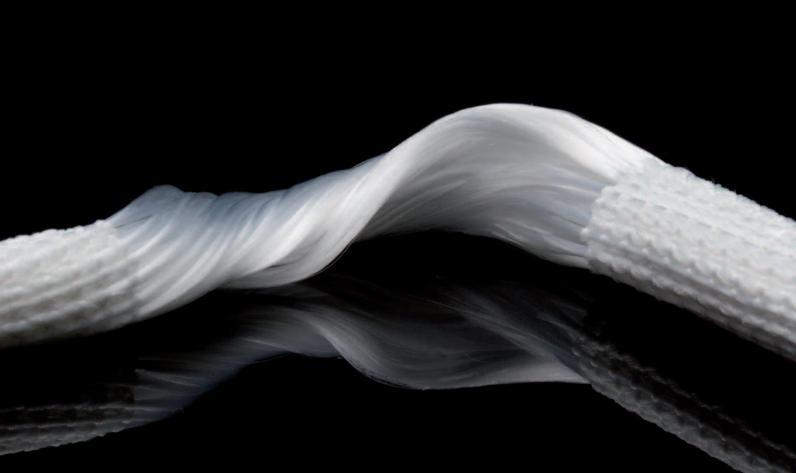

图3 LARS韧带 图4 术中LARS韧带重建

LARS人工韧带为一种新型生物材料,具有优异的生物相容性和力学性能,能够模拟人体自身韧带的生理功能。与传统自体或异体肌腱移植相比,由于人工韧带不需要从自身部位取材,从而减少手术创伤,避免供区疼痛、肌肉力量下降及其它并发症,人工韧带的强度更是人体肌腱的3-4倍,术后便可承受较大的物理负荷,许多患者更早开始康复训练,加快术后恢复过程。